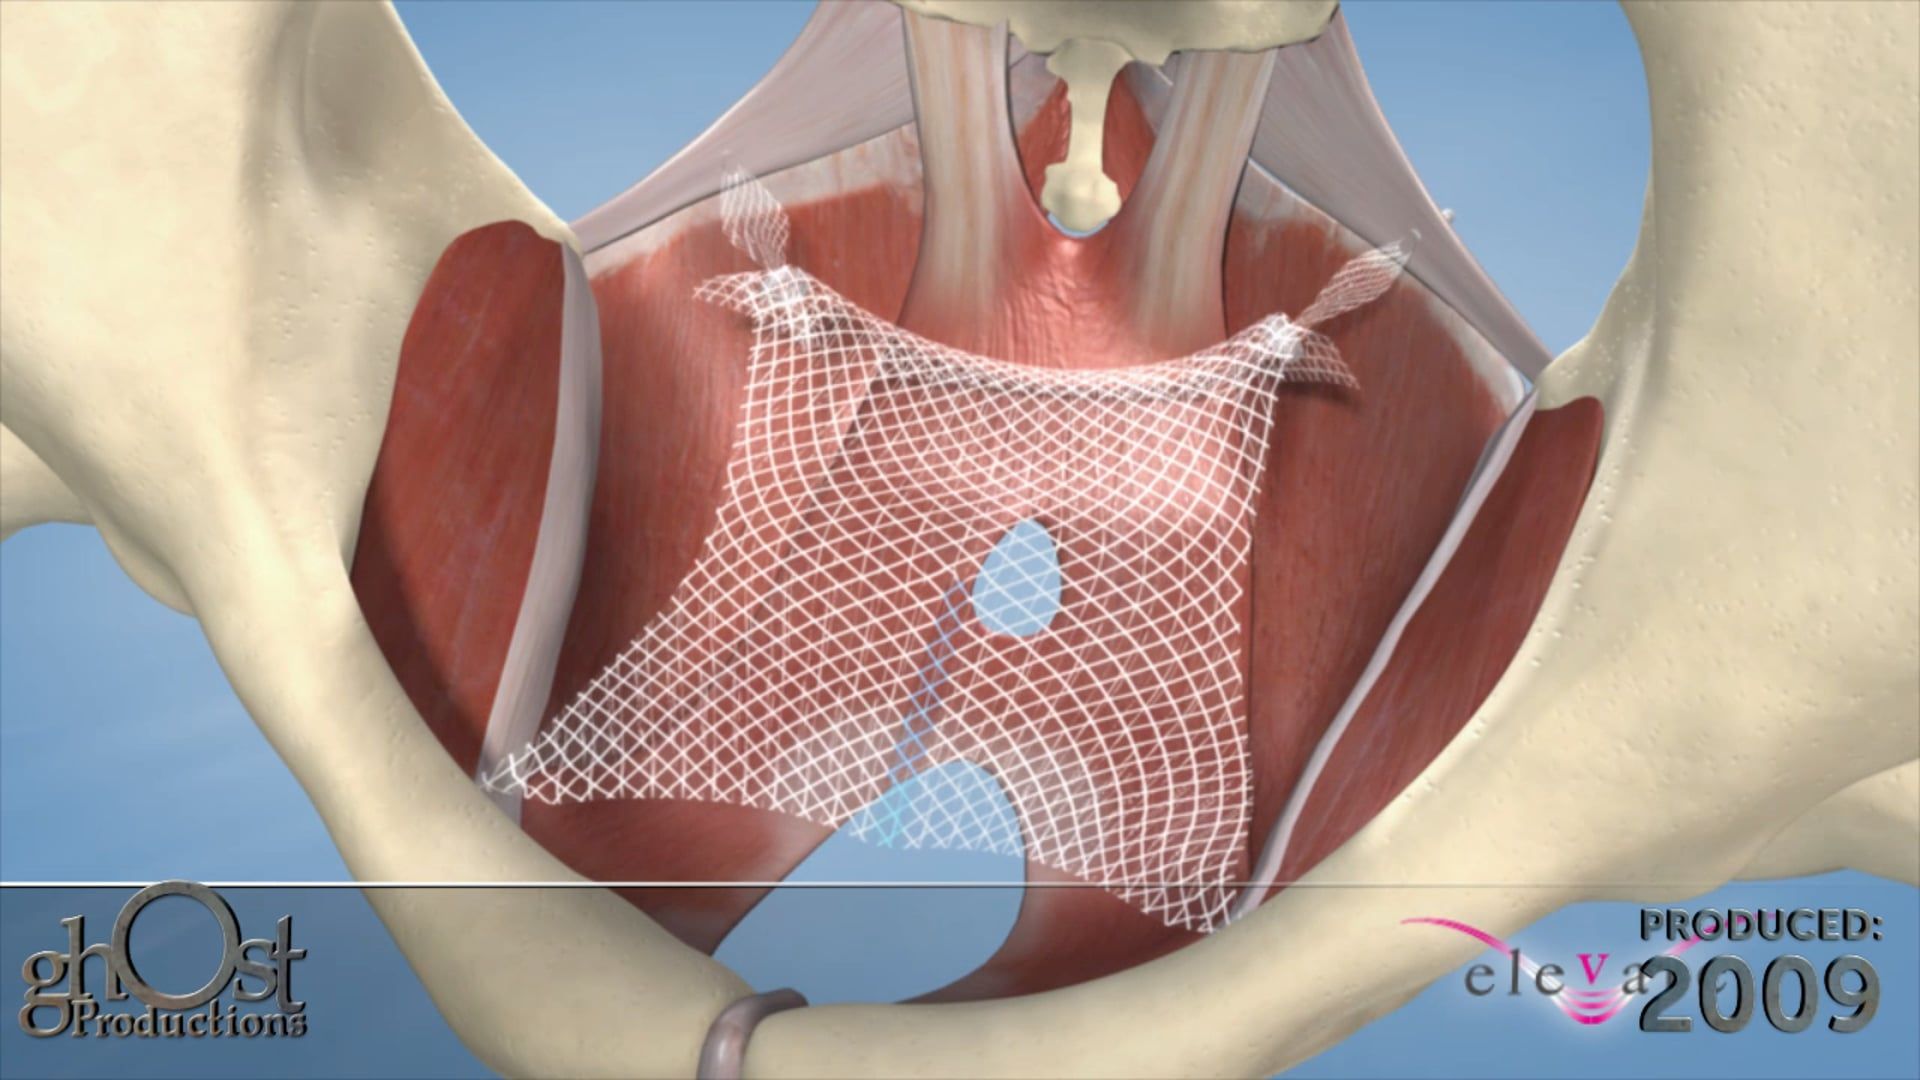

AMS partnered with Ghost Productions, a medical animation and graphics company, to create a series of animations and medical graphics that effectively communicated the benefits of their products. Ghost Productions worked closely with AMS's team to understand the mechanism of action of each product and create a visual representation of the process.

the animations and medical graphics produced by Ghost Productions proved to be instrumental in helping AMS effectively communicate the benefits of their products to their target audience. The visual aids helped potential customers and physicians understand the mechanism of action of each product and the benefits of using them to treat urological and gynecological conditions.